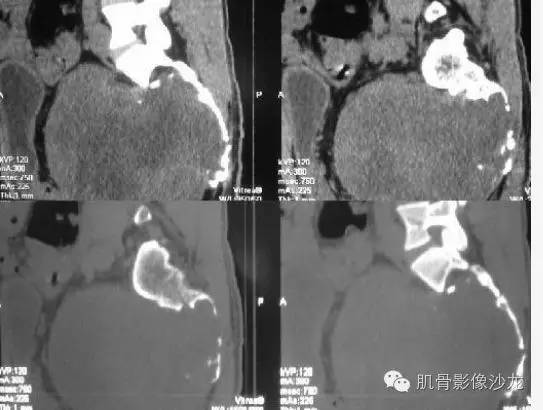

【病例】骶骨神经纤维瘤一例CT影像表现

如果来源骨当属恶性,为何没有一点成骨或钙化什么,倒像破坏残留骨

破坏连续有骨质硬化边,提示破坏修复同时进行,倾向良性生物学行为

软组织肿块边界这么清楚,内部虽然密度不均

脊索看不到多黏液囊,不支持

虽然没有 钙化 ,常规 还是考虑为 脊索瘤啊

患者比较年轻。脊索和淋巴瘤暂不考虑

不考虑脊索

病史:32岁,男性,大小便困难2年,加重伴左侧腰骶部疼痛2个月。

病理:骶骨神经纤维瘤,细胞生长活跃伴局部细胞异型性。